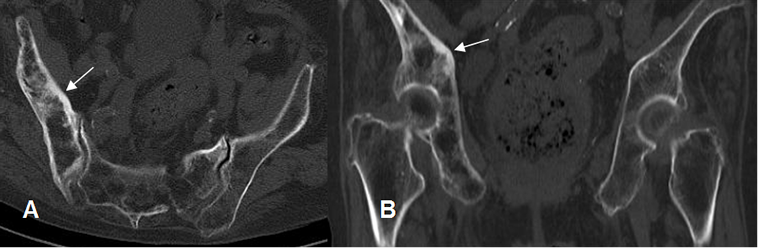

A: TAC axial y B: TAC reconstrucción coronal. Iliaco derecho mas grueso, con engrosamiento de la cortical y aumento de la trabeculación medular, por enfermedad de Paget.

Fig 51. Enfermedad de paget en fase esclerótica.